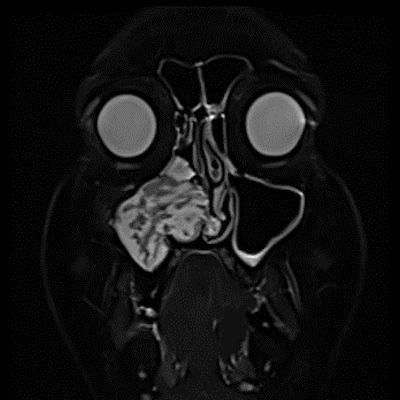

- A) Koronal T2 ağırlıklı görüntülerde sol maksiller sinüs lümenini dolduran, belirgin ‘convoluted’ (karmaşık-kıvrımlı) serebriform patern sergileyen lezyon (oklar), kontrastlı seride heterojen ve yoğun kontrastlanma göstermektedir (oklar). Perfüzyon incelemesinde pedinkülünde perfüzyon artışı gösterdiği, diğer kontrastlanan segmentlerin nispeten hipoperfüze olduğu görülmektedir (ok).